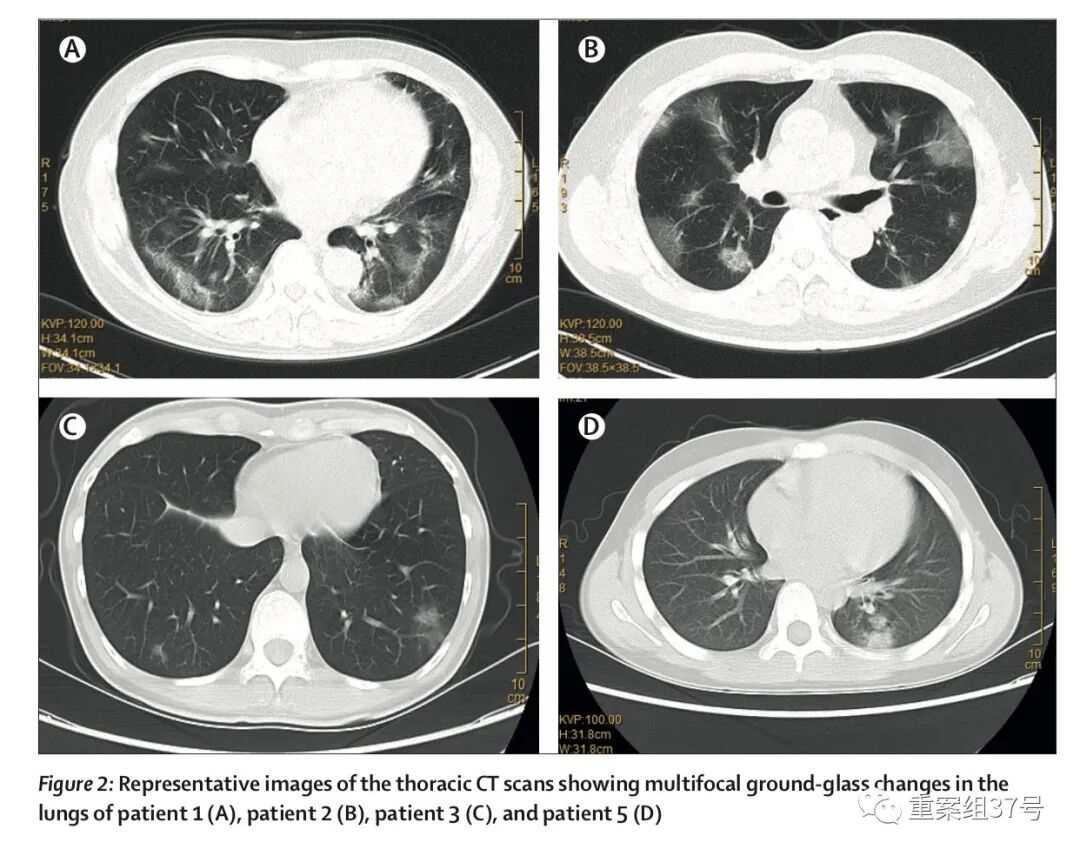

▲有武汉旅行史的返深圳家庭中,多名家庭成员呈现肺部多发磨玻璃样改变,其中10岁的患者为无症状感染者。论文截图